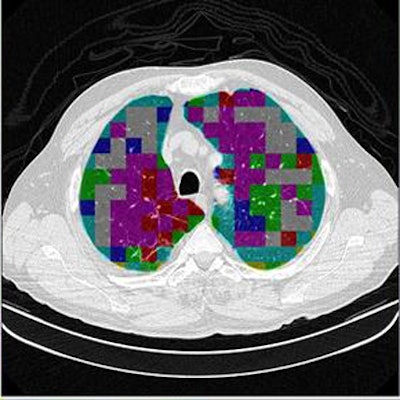

Based on the cross-validation methodology, the classification step delivered an initial average accuracy of 61.6%. However, a confusion matrix analysis showed that the most frequent likely error appeared to be between ground-glass opacities and consolidation, which have similar image profiles.

When the ROIs belonging to these classes were excluded, the average accuracy improved to 78%, Mazzoncini de Azevedo-Marques said.

| The classification algorithm training and test was performed using a 10-fold cross-validation methodology, which classified regions of interest in the lung parenchyma into nine patterns commonly seen on thoracic high-resolution CT images. The background and outside tissue classes indicate regions outside the lungs, while the remaining seven classes refer to patterns found in the lungs: normal parenchyma, ground-glass opacities, reticular and linear opacities, nodular opacities, honeycombing, emphysematous change, and consolidation. The classification step delivered an initial average accuracy of 61.6% (above). Eliminating the two most frequently confused categories, ground-glass opacities and consolidation, improved the average classification accuracy to 78%. |

| The completed CAD-analyzed cases are stored as a new series in the PACS server, where they can be examined side by side. In the color-coding system, normal parenchyma is white; ground-glass regions are blue; reticular-linear, green; micronodules, red; honeycombing, yellow; emphysematous changes, magenta; and consolidation, cyan. |